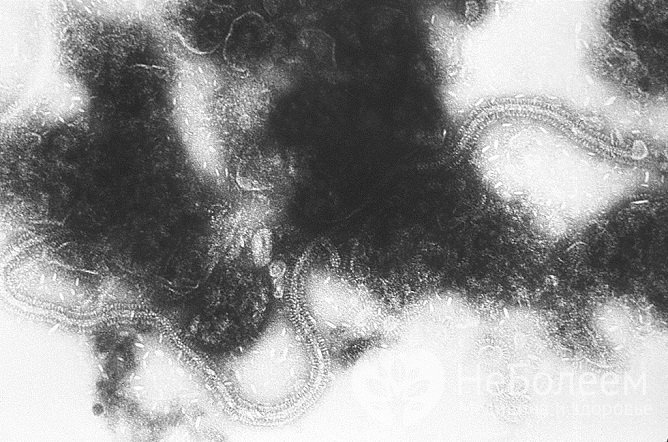

У детей первого года жизни в 80% случаев развитие острого бронхиолита связано с респираторно-синцитиальным вирусом. Значительно реже в качестве возбудителя выступают другие вирусные агенты (коронаровирус, энтеровирус, вирусы гриппа и парагриппа, риновирусы, аденовирусы). После двух лет острый бронхиолит у детей чаще вызывается риновирусами и энтеровирусами. Среди детей дошкольного и младшего школьного возраста наиболее часто в качестве возбудителями заболевания служат риновирусы и микоплазма. Нередко возбудителями острого бронхиолита становятся вирусы простого герпеса, эпидемического паротита (свинки), ветряной оспы и кори, а также хламидии, цитомегаловирус.

У детей первого года жизни бронхиолит в большинстве случаев развивается вследствие респираторно-синцитиального вирусаМалый диаметр бронхов у детей в сочетании с воспалительными изменениями становятся причиной увеличенного сопротивления воздушному потоку. При этом во время выдоха сопротивление больше, чем в момент вдоха. В результате развивается повышенное наполнение воздухом пораженных участков легких, то есть формируется эмфизема.